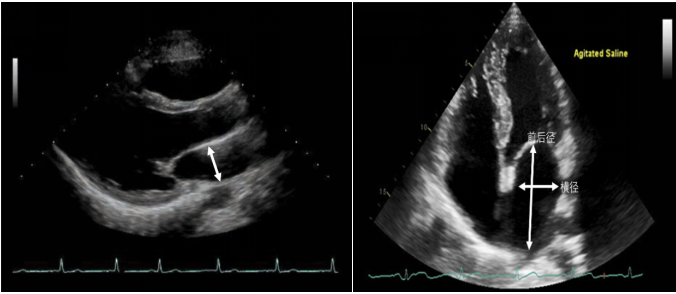

(3)二尖瓣瓣环收缩期位移/长轴缩短量(MAPSE):和三尖瓣TAPSE一样,在心尖四腔心切面,使用M超,瞄准外侧二尖瓣根部,追踪位移水平(图23)。MAPSE的参考值为大于1.3 cm。

图片

图23. M超测量MAPSE

(5)组织多普勒(LV-TDI):心尖四腔心切面,在二尖瓣瓣环处或侧壁处,取样容积5~10 mm进行测量。典型的LV-TDI图像如图25所示。

图25. LV-TDI的测量

收缩期的Sa(s’)峰,舒张早期Ea(e’)峰和舒张晚期Aa(a’)峰。Ea(e’)反映心肌的松弛能力,在侧壁测量的数值高于室间隔壁测量的值,其正常参考值为大于10 cm/s(侧壁)和8 cm/s(室间隔);一般来说,Aa(a’)大于8 cm/s。